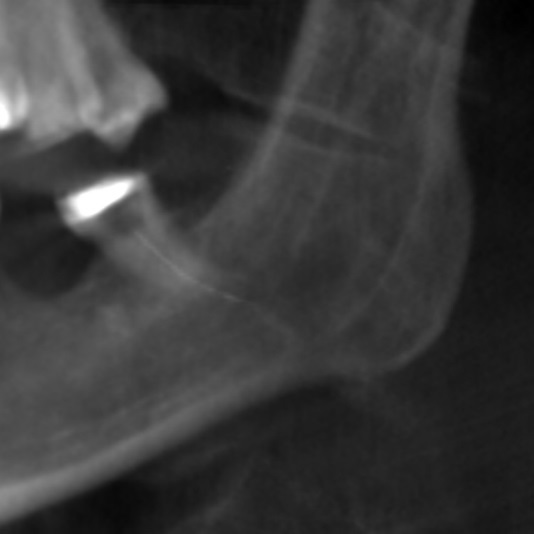

The patient’s symptoms and the close proximity of the broken instrument to the mandibular canal seen in panoramic radiography suggested that the broken endodontic instrument was in contact with the IAN. To confirm this diagnosis, CBCT examination was undertaken, and clearly showed the broken instrument in the periapical area of the mandibular left third molar and that the instrument was inside the mandibular canal. The result was the same as the panoramic examination, broken instrument was noted in the left mandibular canal Figure 3a, Figure 3b.

Figure 3a.CBCT surface examination broken endodontic instrument lodged in the mandibular canal.

Figure 3b.CBCT examination broken endodontic instrument lodged in the mandibular canal.